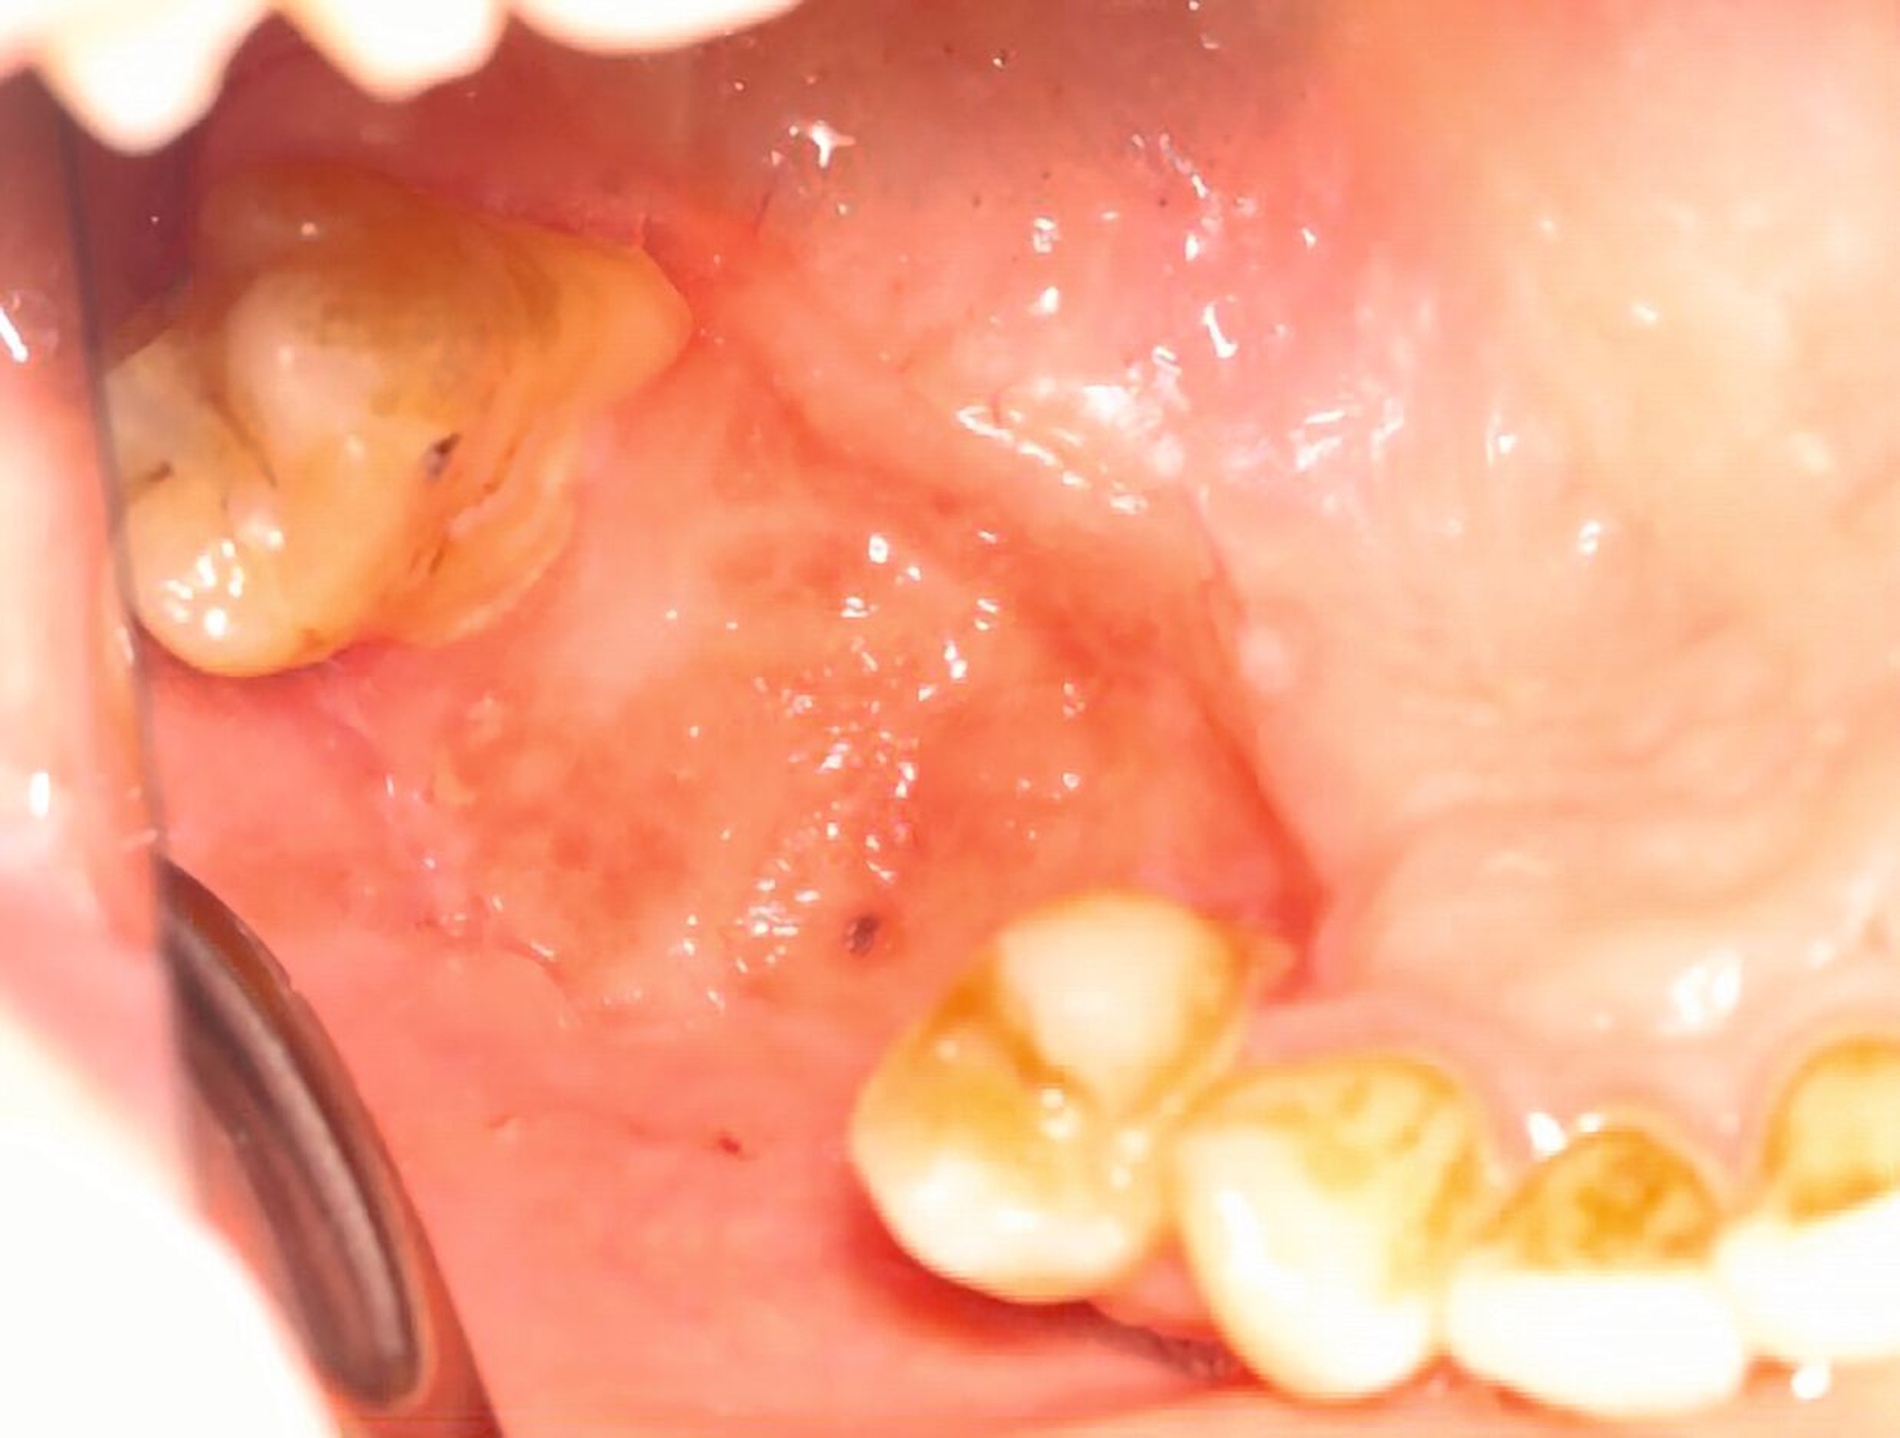

Die klinische Untersuchung zeigte eine ausgeprägte nekroische Schleimhaut palatinal und vestibulär regio 15 bis 17, einen stark gelockerten Zahn 15 sowie einen intensiven Foetor ex ore bei einer auf 2,5 cm eingeschränkten Mundöffnung (Abbildung 1).

Das DVT zeigte eine Spiegelbildung im rechten Sinus maxillaris, jedoch keinen stark auffälligen knöchernen Befund (Abbildung 2). Die Patientin wurde zu intravenöser Antibiose, Analgesie und Ernährung über eine nasogastrale Sonde stationär aufgenommen. Im Verlauf wurde eine Verbandsplatte per Intraoralscan angefertigt und eine Operation zur Nekrosektomie und Wundanfrischung geplant. Zum Zeitpunkt des operativen Eingriffs hatten sich bereits Teile der vestibulären und der palatinalen Schleimhaut abgelöst. Nach Debridement zeigte sich ein großflächiges Areal mit freiliegendem Knochen. Der Zahn 15 wurde bei Lockerungsgrad III entfernt (Abbildung 3).